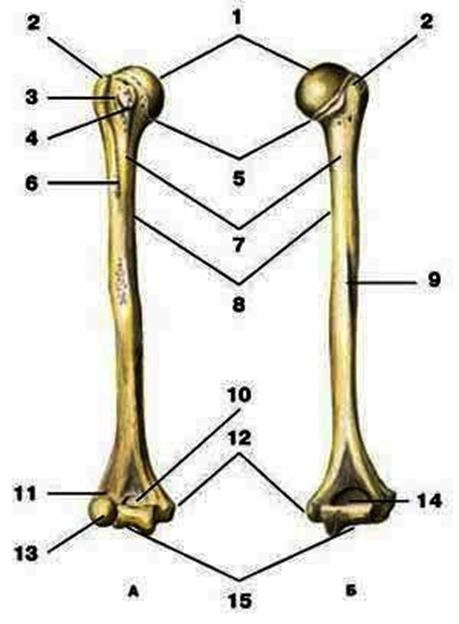

V2:Тема 1.3 Кости верхней конечности и их соединения

S: Цифра 1 обозначает … плечевой кости.

+:сaput

-:t uberculum majus

-:troсhlea

-:capitulum

-:epicondylus lateralis

S: Число 15 обозначает... плечевой кости.

+:trochlea

S: Цифра 5 указывает на...плечевой кости.

+:collum anatomicum

S: Число 10 обозначает... плечевой кости.

+:fossa coronoidea

S: Число 14 указывает на... плечевой кости.

+:fossa olecrani

S: Цифра 9 указывает на... плечевой кости.

+:sulcus nervi radialis

S: Число 12 обозначает... плечевой кости.

+:epicondylus medialis